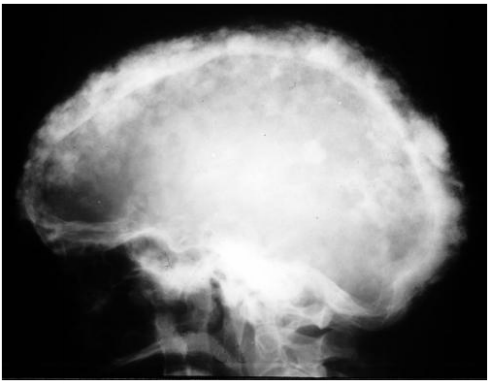

78.一位22歲男性患者之環口X光顯示兩側下顎臼齒下方有周界清晰之放射線透性(radiolucent)影像(圖A如箭頭標示),兩側上顎竇 亦有放射線不透性(radiopaque)影像,手術發現此病變為齒源性角化囊腫(odontogenic keratocysts);進一步檢查發現中面部 有一潰瘍病變(圖B),腳掌有許多黑色凹點病灶(圖C),臉部呈現眼距過寬,頭部X光可見大腦鐮鈣化(calcification of falx cerebri)(圖D),胸部X光片可見到分歧肋骨(bifid ribs)。根據這些特徵,下列何診斷較可能?

(A)Gardner syndrome (B)Nevoid basal cell Carcinoma Syndrome (C)McCune-Albright syndrome (D)Apert syndrome